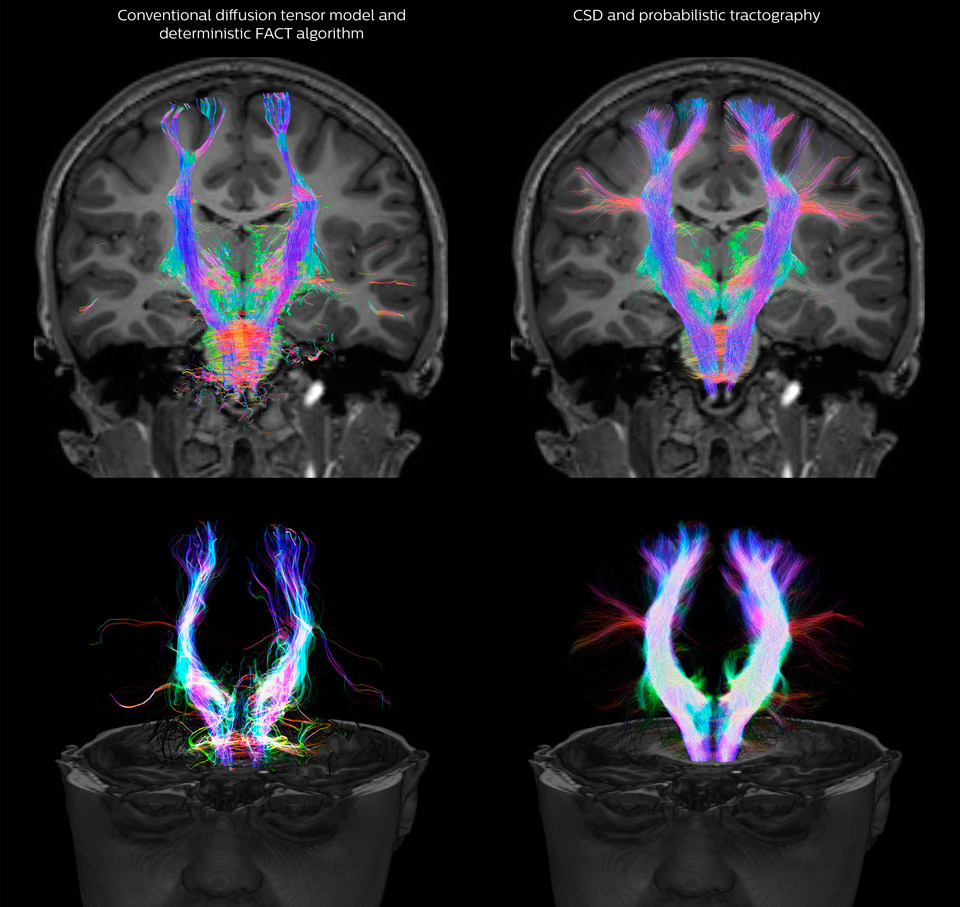

Comparison of fiber tractography methods

Fiber tractography of the corticospinal tract with seed region of the posterior limb of the internal capsule. Different processing based on the same data.

UVM research comparison of fiber tractography methods

All images were created from the same acquisition in a child using Ingenia 3.0T CX and 32-channel dS Head coil. Diffusion data was acquired at b-values 0, 500, 1000, 2000, 3000. The use of high b-values (3000 s/mm2) effectively suppresses extra-axonal water signal and provides high angular resolution.

Legend of acronyms

CSD: constrained spherical deconvolution

DEC TDI: directionally encoded color track-density imaging

DTI: diffusion tensor imaging

DWI: diffusion-weighted imaging

FOD: fiber orientation density

Data processing was performed using open source software. Fiber tracking was performed using the MRtrix package (J-D Tournier, Brain Research Institute, Melbourne, Australia, https://github.com/MRtrix3/mrtrix3), Tournier et al. 2012. DEC TDI based on F Calamante et al 2010.